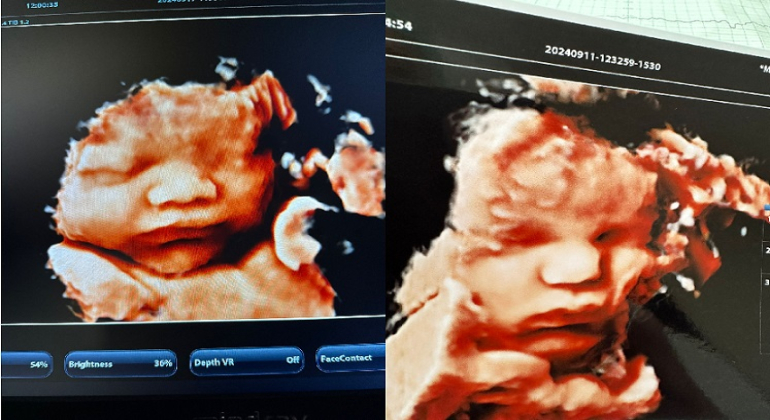

Gebelikte Dört Boyutlu (4D) Ultrasonografi Nedir?

Op. Dr. Muzaffer ŞENGÜL